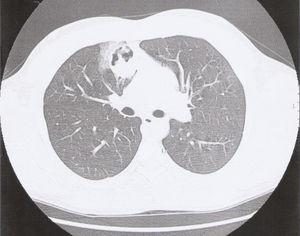

A 24-year-old man, a non-smoker, presented at the emergency department with complaints of cough, haemoptysis, dyspnoea on exertion, fever (38 °C) and excessive sweating at night, with two days of evolution. He had no relevant pathologic background, and physical examination was normal. On the chest X-ray we found a right infrahilar shadow, the bronchoscopy was normal as were the respiratory function and the blood tests. The first computed tomography (CT) of the chest showed a 44 mm heterogeneous (well-circumscribed and probably cavitated) ovoid mass (Figure 1), located in the inner right upper lobe, near the middle lobe. The differential diagnosis was lung abscess, round pneumonia, pulmonary tuberculosis, aspergilloma and tumour. After a 3-week course of antibiotics, a second CT, now with intravenous iodinated contrast, showed a homogenous mass of the same size and location, and the patient was transferred for surgical evaluation, and resection of the right upper and middle lobe. Histopathological examination revealed spindle cell proliferation, with storiform or fascicular pattern, with foci of haemorrhage, inflammatory infiltrate of lymphocytes, neutrophils, eosinophils and aggregates of foam cell (Figure 2). Rare Touton giant cells were also found. No significant cytological atypia was identified. The neoplastic cells were diffusely and strongly positive for immunostaining for ALK and histiocytic marker CD163, while weakly and focally positive for smooth muscle marker SMA and cytokeratin CAM5.2.

Figure 1. Ovoid mass in the first CT of the chest.